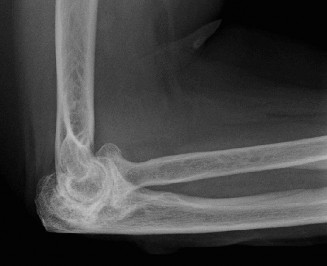

Physically examine a patient for classic posterolateral instability? Understand the potential treatment options? CASE 37 A 53-year-old, left-hand-dominant male presents to your office for evaluation regarding his elbow pain. He states that for the past 5 years he has had pain in his left elbow. It seems to be worsening over the past 6 months. He states he works as a mechanic and the pain is limiting the amount of time he can spend working. He takes anti-inflammatories with some relief. His images are shown (Figs. 2–97 and 2–98).

Figure 2–97

Figure 2–98

Which of the following symptoms is common in the early stages of osteoarthritis (OA)?

The correct answer is (A). Pain when carrying heavy objects with the elbow in extension is a classic presentation for patients with early disease. They also have

motion loss less than 15 degrees and respond well to conservative treatments. Patients with intermediate disease have moderate pain at the ends of motion, often have loss of extension >30 degrees and have ulnar nerve symptoms. Patients with end-stage OA have pain in the mid-arc of motion, have failed conservative treatment and have motion loss greater than 30 degrees.